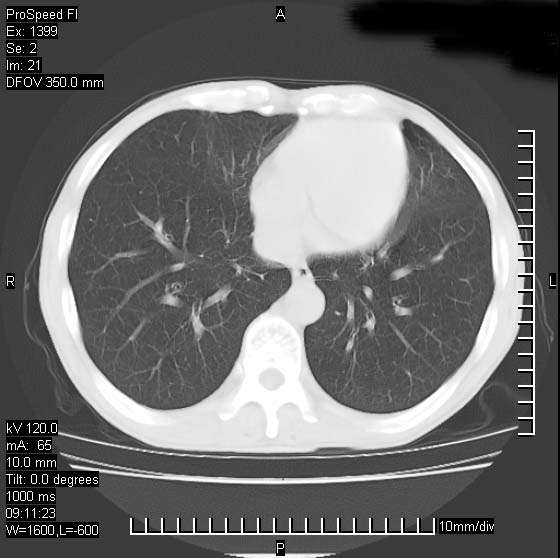

以下是引用卜一在2007-1-19 9:55:00的发言:[br]左肺沿胸膜下巨大肿块影,边缘呈分叶征,纵隔内见肿大淋巴结,右肺内另见一不规则结节影 .考虑:左肺周围性肺癌伴纵隔 右肺内转移.

以下是引用rgsyyf在2007-1-19 11:05:00的发言:[br]左肺上叶见形态不规则巨大软组织肿块影,边缘呈分叶征,纵隔内隆突下见肿大淋巴结,右肺内另见一不规则结节影 .考虑:左肺周围性肺癌伴纵隔即右肺内转移.